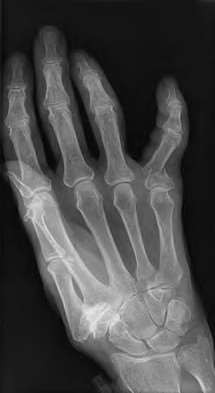

A 35-year-old woman reports wrist pain after a fall onto an outstretched hand. On exam, she has focal tenderness over the wrist snuffbox. A radiograph and CT image are shown in Figures A and B. What is the proper treatment of her injury?